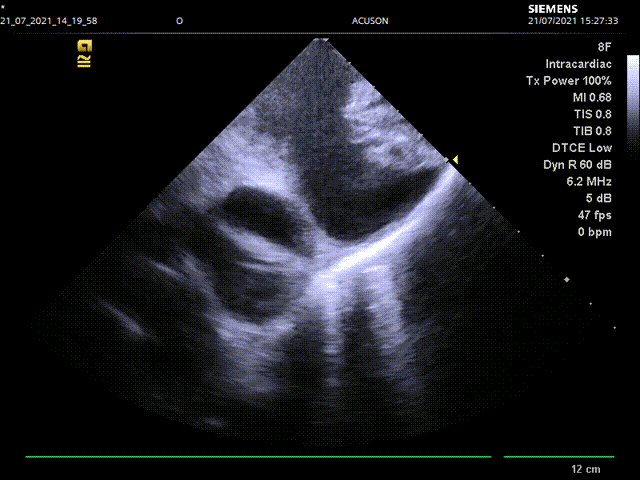

手术主要流程:经右股静脉入路,通过房间隔穿刺,将8F ICE导管送入左心房,在左心房通过三个不同的位置和角度测量左心耳锚定区大小和深度:左上肺静脉脊部角度、右肺静脉角度,二尖瓣环角度。而后进行左心耳造影,多种方式测量左心耳大小,选择合适病人情况的封堵器。放置左心耳封堵器后再用同样位置角度评估封堵情况。

心腔内超声左房内右肺静脉前测量左心耳开口锚定区和深度

心腔内超声左房内右肺肺静脉前评估封堵情况